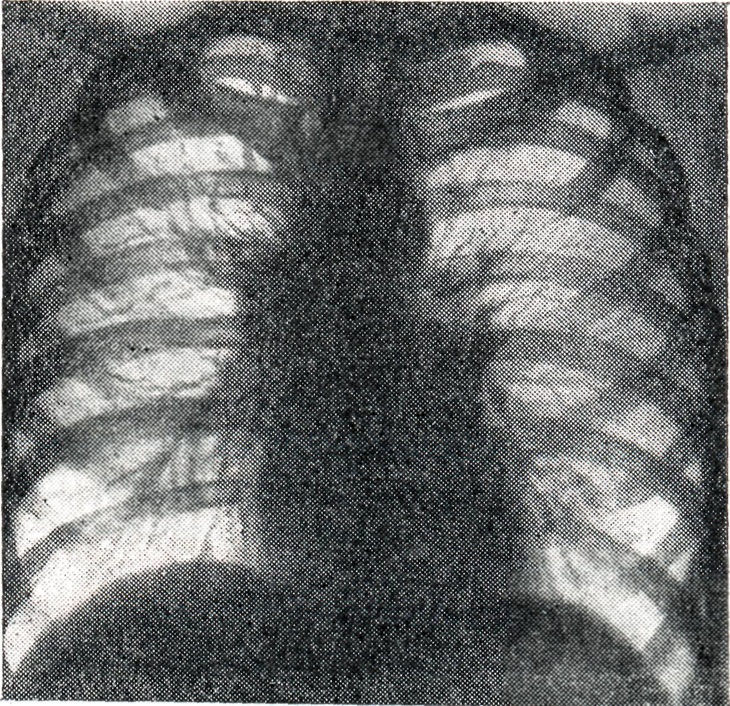

Рис. 1.

Двусторонний опухолевидный бронхаденит. Тени корней увеличены, контурируются довольно чёткими волнообразными линиями (рентгенограмма).

При опухолевидной форме Б. перифокальные явления в прилегающей лёгочной ткани обычно отсутствуют. Тень корня увеличена, менее структурна, отдельные сосудистые стволы корня плохо различимы (рис. 1).

Проекции бронхов менее отчётливы, тень корня почти сливается с тенью средостения. Наружная волнообразная или бугристая граница деформированного корня проецируется в виде отчётливой, хотя и не всегда резкой линии, что зависит от отсутствия или наличия воспалительных изменений в капсуле лимф, узлов. При одностороннем опухолевидном Б. изменения корня противоположного лёгкого менее выражены (рис. 2), на стороне поражения лёгочный рисунок несколько усилен, прилежащие листки междолевой плевры уплотнены (рис. 3).